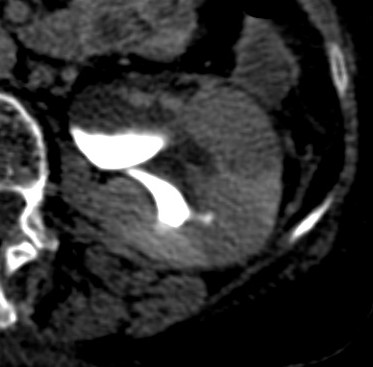

Se procede a realizar TC abdomino-pélvico con contraste en fase nefrográfica y excretora:

Conclusión: se nos presentó un caso de un paciente con una sospecha de infección renal complicada ya que tras cuatro días de tratamiento antibiótico no hubo mejoría. Ante los hallazgos observados en TC, podemos establecer el diagnóstico de pieloureteritis renal izquierda con signos de hidroureteronefrosis leve hasta vejiga.

- Protocolo: TC abominopélvico sin y con contraste en fase nefrográfica (70 seg) +/- fase tardía ( a los 7 – 10 min) solo si se sospecha obstrucción.

- TC con contraste: Las áreas afectadas del parénquima aparecen como zonas con baja atenuación debido al edema. Las áreas hiperdensas son menos frecuentes y corresponden a focos de hemorragia. Estos hallazgos son mejor valorables a través de la aplicación de contraste, ya que un TC en vacío pueden pasar desaprecibidas.